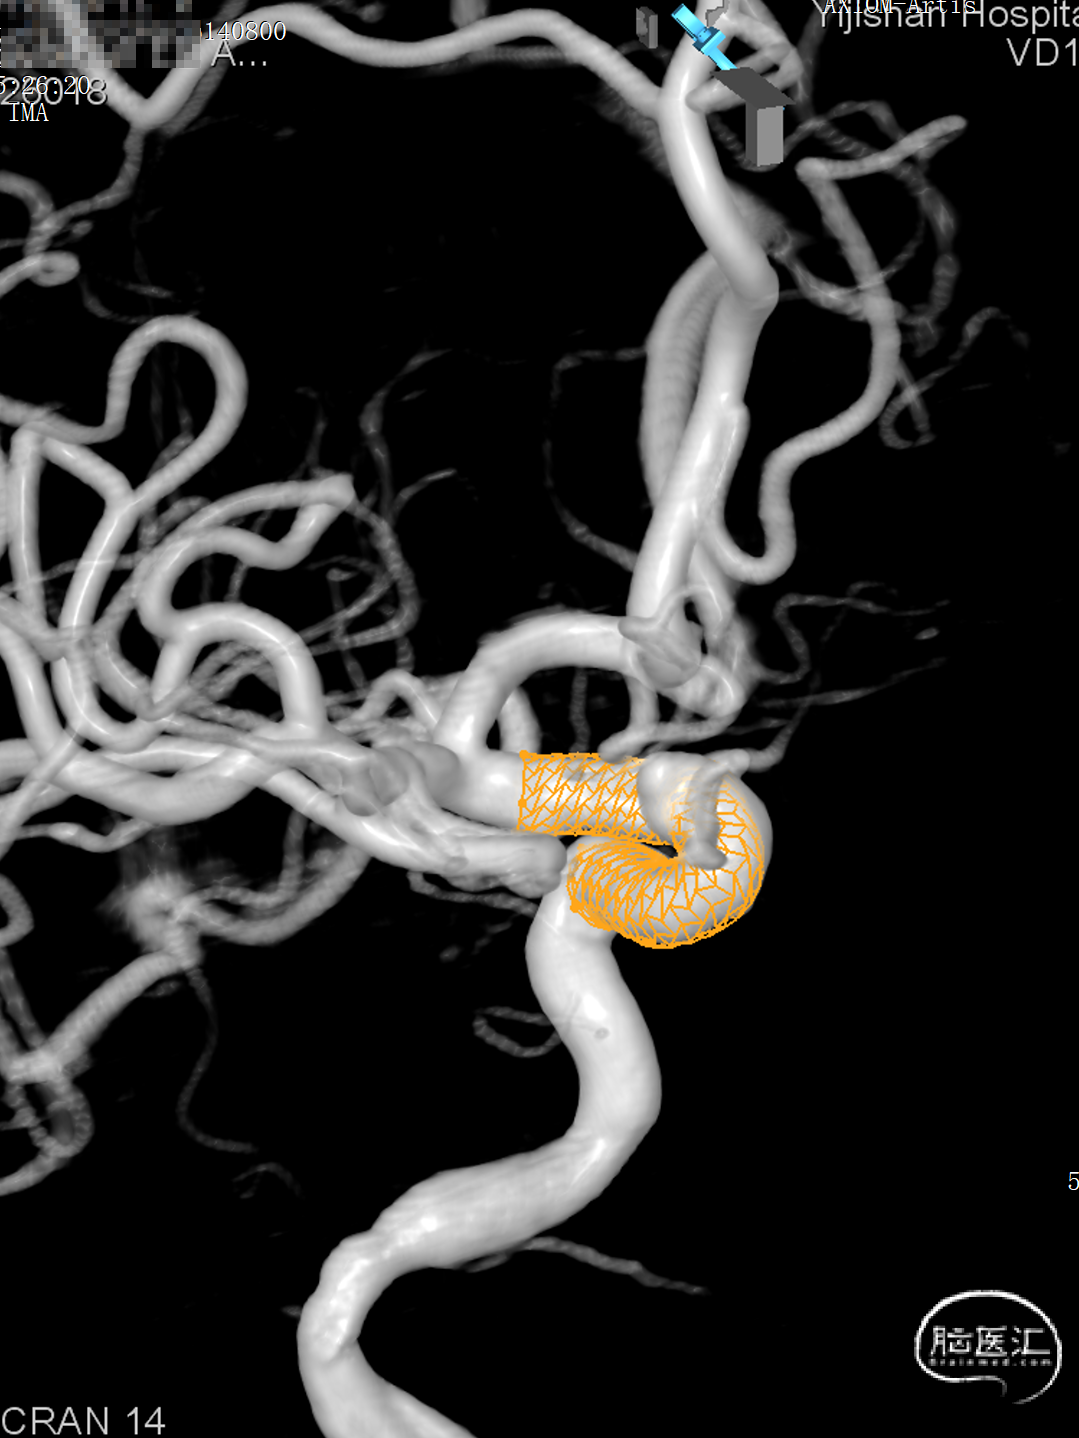

➢ 术前动脉瘤3D

右侧颈内动脉眼动脉段动脉瘤,动脉瘤锥型宽基底,瘤宽6.67mm,瘤高3.68mm,动脉瘤血管远端直径4.86mm,近端直径4.95mm,拟采用密网型号5.0mm*25mm。

通桥麒麟™血流导向密网支架释放模拟图。